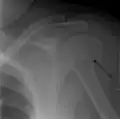

Humerus fracture

Definitive diagnosis of humerus fractures is typically made through radiographic imaging. For proximal fractures, X-rays can be taken from a scapular anteroposterior (AP) view, which takes an image of the front of the shoulder region from an angle, a scapular Y view, which takes an image of the back of the shoulder region from an angle, and an axillar lateral view, which has the patient lie on his or her back, lift the bottom half of the arm up to the side, and have an image taken of the axilla region underneath the shoulder.[9] Fractures of the humerus shaft are usually correctly identified with radiographic images taken from the AP and lateral viewpoints.[12] Damage to the radial nerve from a shaft fracture can be identified by an inability to bend the hand backwards or by decreased sensation in the back of the hand.[5] Images of the distal region are often of poor quality due to the patient being unable to extend the elbow because of pain. If a severe distal fracture is suspected, then a computed tomography (CT) scan can provide greater detail of the fracture. Nondisplaced distal fractures may not be directly visible; they may only be visible due to fat being displaced because of internal bleeding in the elbow.[7]